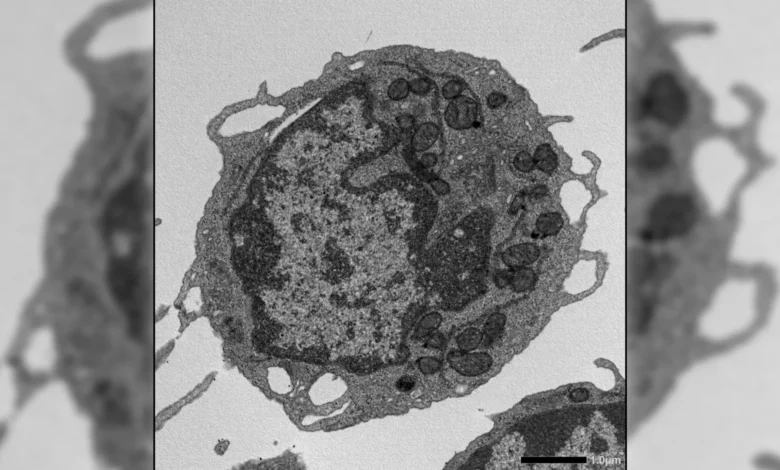

Complementing these functional assays, the researchers employed a suite of advanced molecular and cellular biology tools. Flow cytometry provided detailed analysis of cell populations. Ex vivo expansion allowed for the study of HSCs outside the body. RNA sequencing (RNA-seq) offered a comprehensive look at gene expression profiles, while assay for transposase-accessible chromatin using sequencing (ATAC-seq) revealed insights into the accessibility of DNA, indicative of gene regulatory activity. High-resolution imaging allowed for detailed visualization of cellular structures, metabolic testing provided information on cellular energy production, and meticulous studies of mitochondria, the powerhouses of the cell, were conducted. This multi-pronged approach enabled a holistic examination of MLKL’s influence on HSCs at various levels of biological organization.

When activated in response to cellular stress, MLKL exhibited a transient translocation to the mitochondria. Within these critical energy-generating organelles, MLKL instigated damage. This damage manifested as a decrease in mitochondrial membrane potential, alterations in mitochondrial structure, and a significant reduction in cellular energy production. These mitochondrial dysfunctions, in turn, directly contributed to hallmark characteristics of aging in HSCs. The stem cells displayed a diminished capacity for self-renewal, a reduced output of lymphoid cells essential for adaptive immunity, and a pronounced skewing towards the production of myeloid cells, which are often associated with inflammation. This finding represents a significant departure from the canonical understanding of MLKL’s function, highlighting its potential as a modulator of cellular function beyond its role in cell demise.